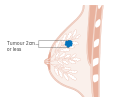

Stage T1 breast cancer